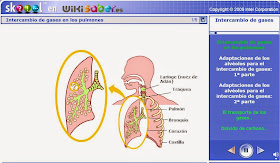

10.1. Inspiración En ella los músculos intercostales externos se contraen y suben las costillas y el esternón, en cambio el diafragma desciende. Todo ello aumenta la capacidad de la caja torácica, provocando que los pulmones se dilaten y entre aire rico en O2. Mediante la inspiración el aire entra por los orificios nasales donde es calentado, humedecido y parcialmente limpiado con ayuda del moco del interior. Los pelos situados en los orificios nasales retienen las partículas más grandes. Por otra parte, el moco y las células con cilios de las fosas nasales, la tráquea y los bronquios retienen las pequeñas partículas y las envían lentamente hacia la garganta, siendo después expectorado o deglutido.   ANIMACIONES       10.2. Intercambio de gases En ella el aire húmedo, limpio, caliente y rico en O2, llega hasta los alvéolos pulmonares, las paredes de los cuales son tan finas que permiten el intercambio gaseoso. Como están recubiertos de finos capilares sanguíneos que contienen sangre cargada de CO2 y pobre en O2, el CO2 pasa al interior de los alvéolos y el O2 pasa a la sangre que hay en los capilares sanguíneos. La membrana del alvéolo pulmonar es muy fina, sólo 0,6 micras (0,6µ) y las paredes que los separan son permeables a ellos. Debido a todo ello los gases pueden pasar de unos a los otros. El resultado es que ambas mezclas de gases acaban teniendo una composición muy parecida. La sangre que sale de los capilares sanguíneos que recubren los alvéolos pulmonares hacia el corazón es rica en oxígeno y muy pobre en dióxido de carbono.    ANIMACIONES            CUESTIONES: 18 19 48 49 10.3. Espiración Es un proceso activo que se produce cuando los pulmones aumentan de volumen gracias a la contracción de los músculos intercostales que elevan las costillas, los músculos pectorales y el diafragma (que se aplana). Los pulmones no están directamente unidos a la caja torácica, sino que están separados por las pleuras. Cuando las costillas y el diafragma tiran de una de estas membranas, la otra, que está unida a los pulmones, es también atraída. Normalmente, inspiramos unas 12-16 veces por minutos, y espiramos otras tantas; pero en situaciones de necesidad inspiramos hasta 40 o más veces por minuto El aire cargado de dióxido de carbono será expulsado a la atmósfera mediante la espiración que generalmente es un proceso pasivo (se produce cuando los músculos respiratorios se relajan y disminuye así el volumen de la caja torácica).   ANIMACIONES          |

El bronquio que penetra en cada pulmón se va ramificando y da numerosos tubos estrechos llamados bronquiolos, estos finalizan en ensanchamientos llamados sacos alveolares. Cada saco alveolar contiene numerosos alvéolos, en ellos es donde se realizará el intercambio gaseoso. Rodeando a los sacos alveolares aparecen multitud de pequeños vasos sanguíneos llamados capilares.

Considerando los dos pulmones hay unos 500 millones de alvéolos pulmonares.

- Arteria pulmonar. Contiene sangre pobre en oxígeno y rica en dióxido de carbono, que se mueve desde el corazón hacia los pulmones.

- Vena pulmonar. Contiene sangre rica en oxígeno y pobre en dióxido de carbono que se mueve desde los pulmones hacia el corazón.

En los alvéolos pulmonares es donde se produce el intercambio de gases entre el aire y la sangre, en función de la concentración de oxígeno y dióxido de carbono.